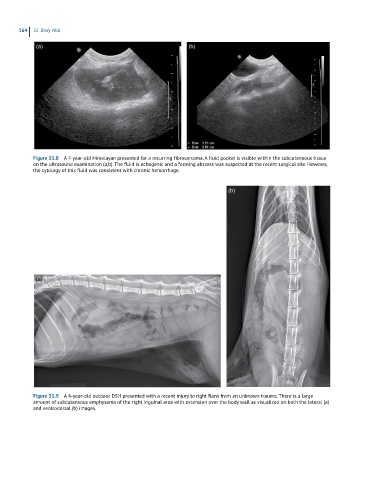

Figure 31.8 A 7-year-old Himalayan presented for a recurring fibrosarcoma. A fluid pocket is visible within the subcutaneous tissue

on the ultrasound examination (a,b). The fluid is echogenic and a forming abscess was suspected at the recent surgical site. However,

the cytology of this fluid was consistent with chronic hemorrhage.

Figure 31.9 A 4-year-old outdoor DSH presented with a recent injury to right flank from an unknown trauma. There is a large

amount of subcutaneous emphysema of the right inguinal area with extension over the body wall as visualized on both the lateral (a)

and ventrodorsal (b) images.